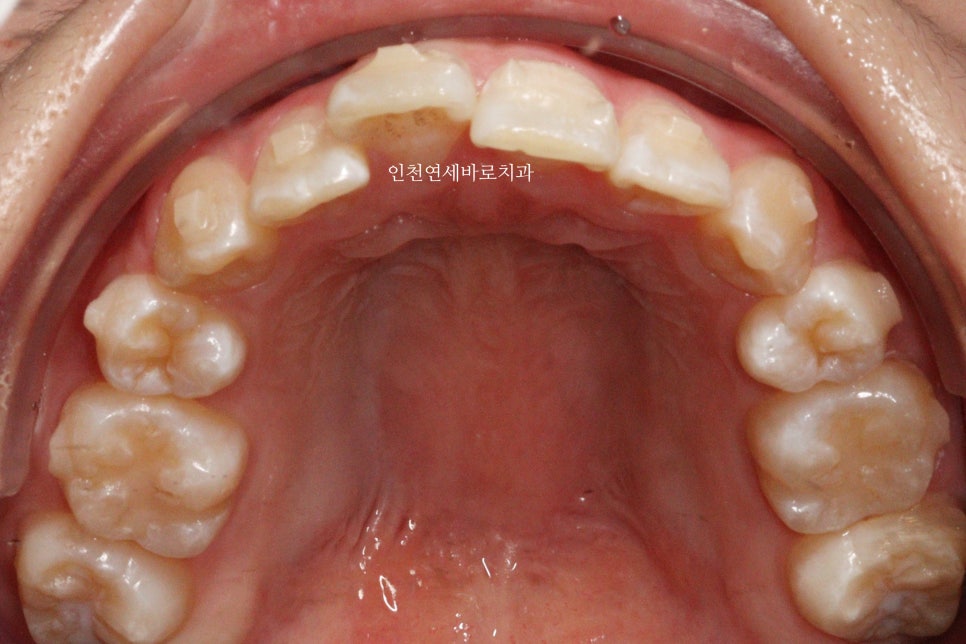

변화모습입니다.

장치의 제작이 한달이나 걸리기 때문에 3/30이 처음 교정치료를 시작했던 날입니다.

약 3개월의 변화모습입니다.